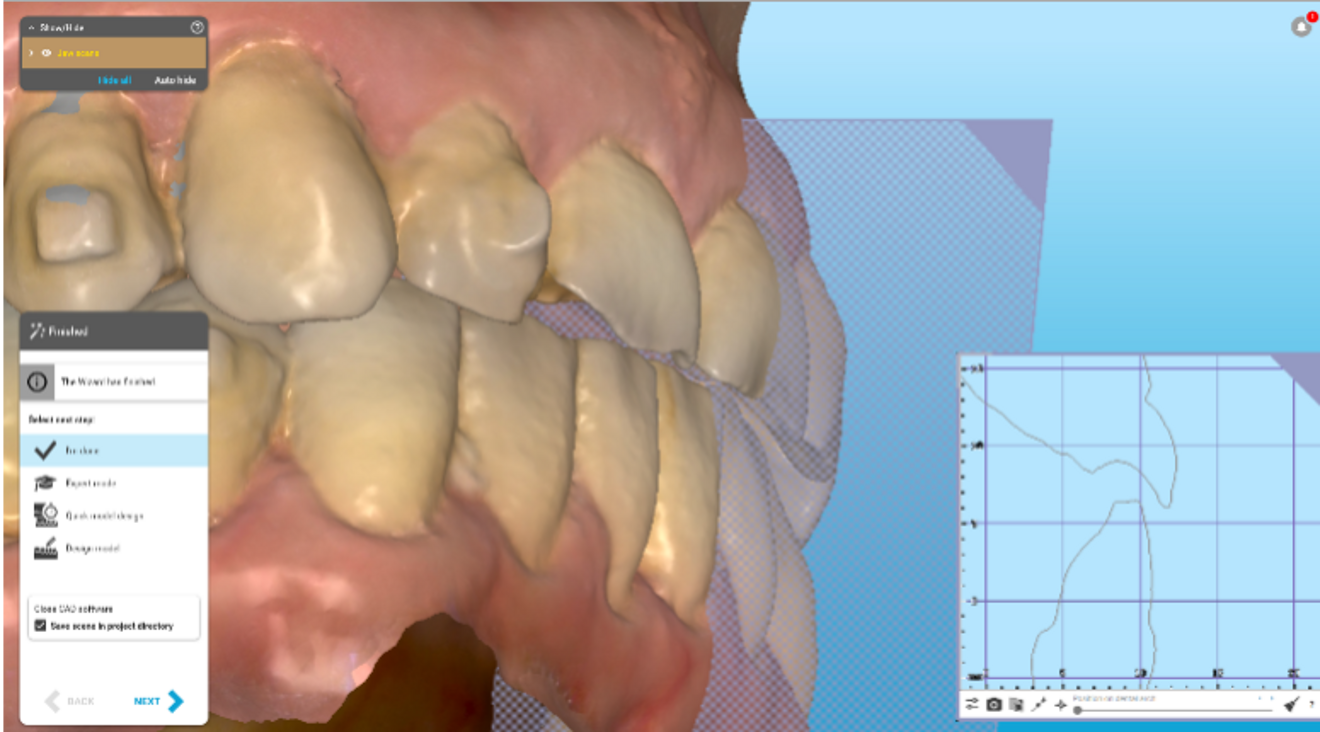

The importance of aligner compliance was stressed, and the patient progressed well with treatment, which included take-home whitening along with the aligner therapy. Analysis of the situation after aligner therapy was performed, including review with exocad software (Figs. 2–5). This was followed by the placement of anterior resin composite restorations (IPS Empress Direct, Bleach-L Dentin; Ivoclar). No preparation or reduction of the remaining dentition was performed—instead, space was created via preparation with plastic.

Figs. 3a & b: Side-by-side lingual view of the pre- (a) and post-alignment ClinCheck images (b) with restorative overlay displaying orthodontic space creation for the restorative and prosthodontic phase of treatment.